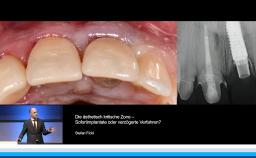

ITI Online Study Club Oldenburg: "Weichgewebsmanagement um Implantate in der ästhetischen und funktionellen Zone" (Referent: Professor Stefan Fickl)